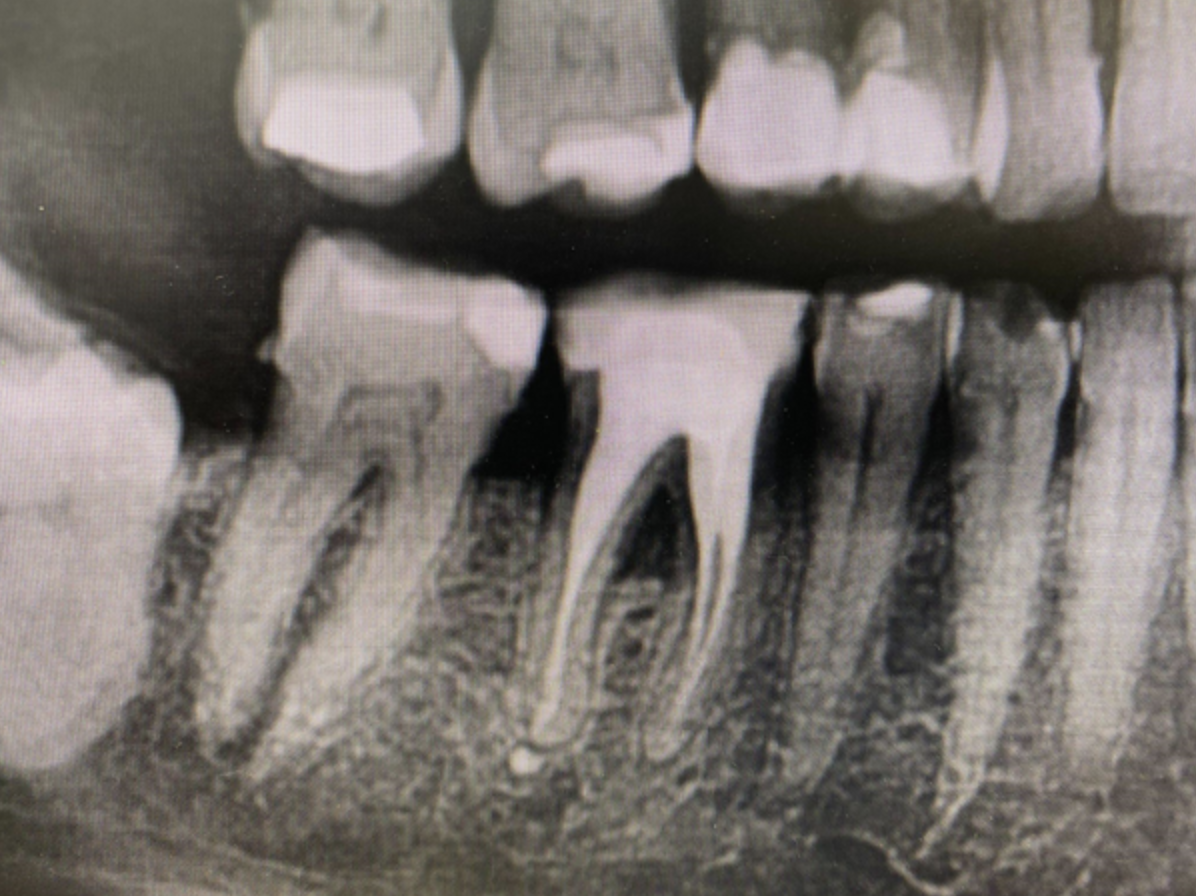

Zdj. 2 Próchnica i liczne korzenie zgorzelinowe

Zdj. 4 Zanik furkacji - gromadzące się resztki pokarmowe mogą dać efekt halitozy